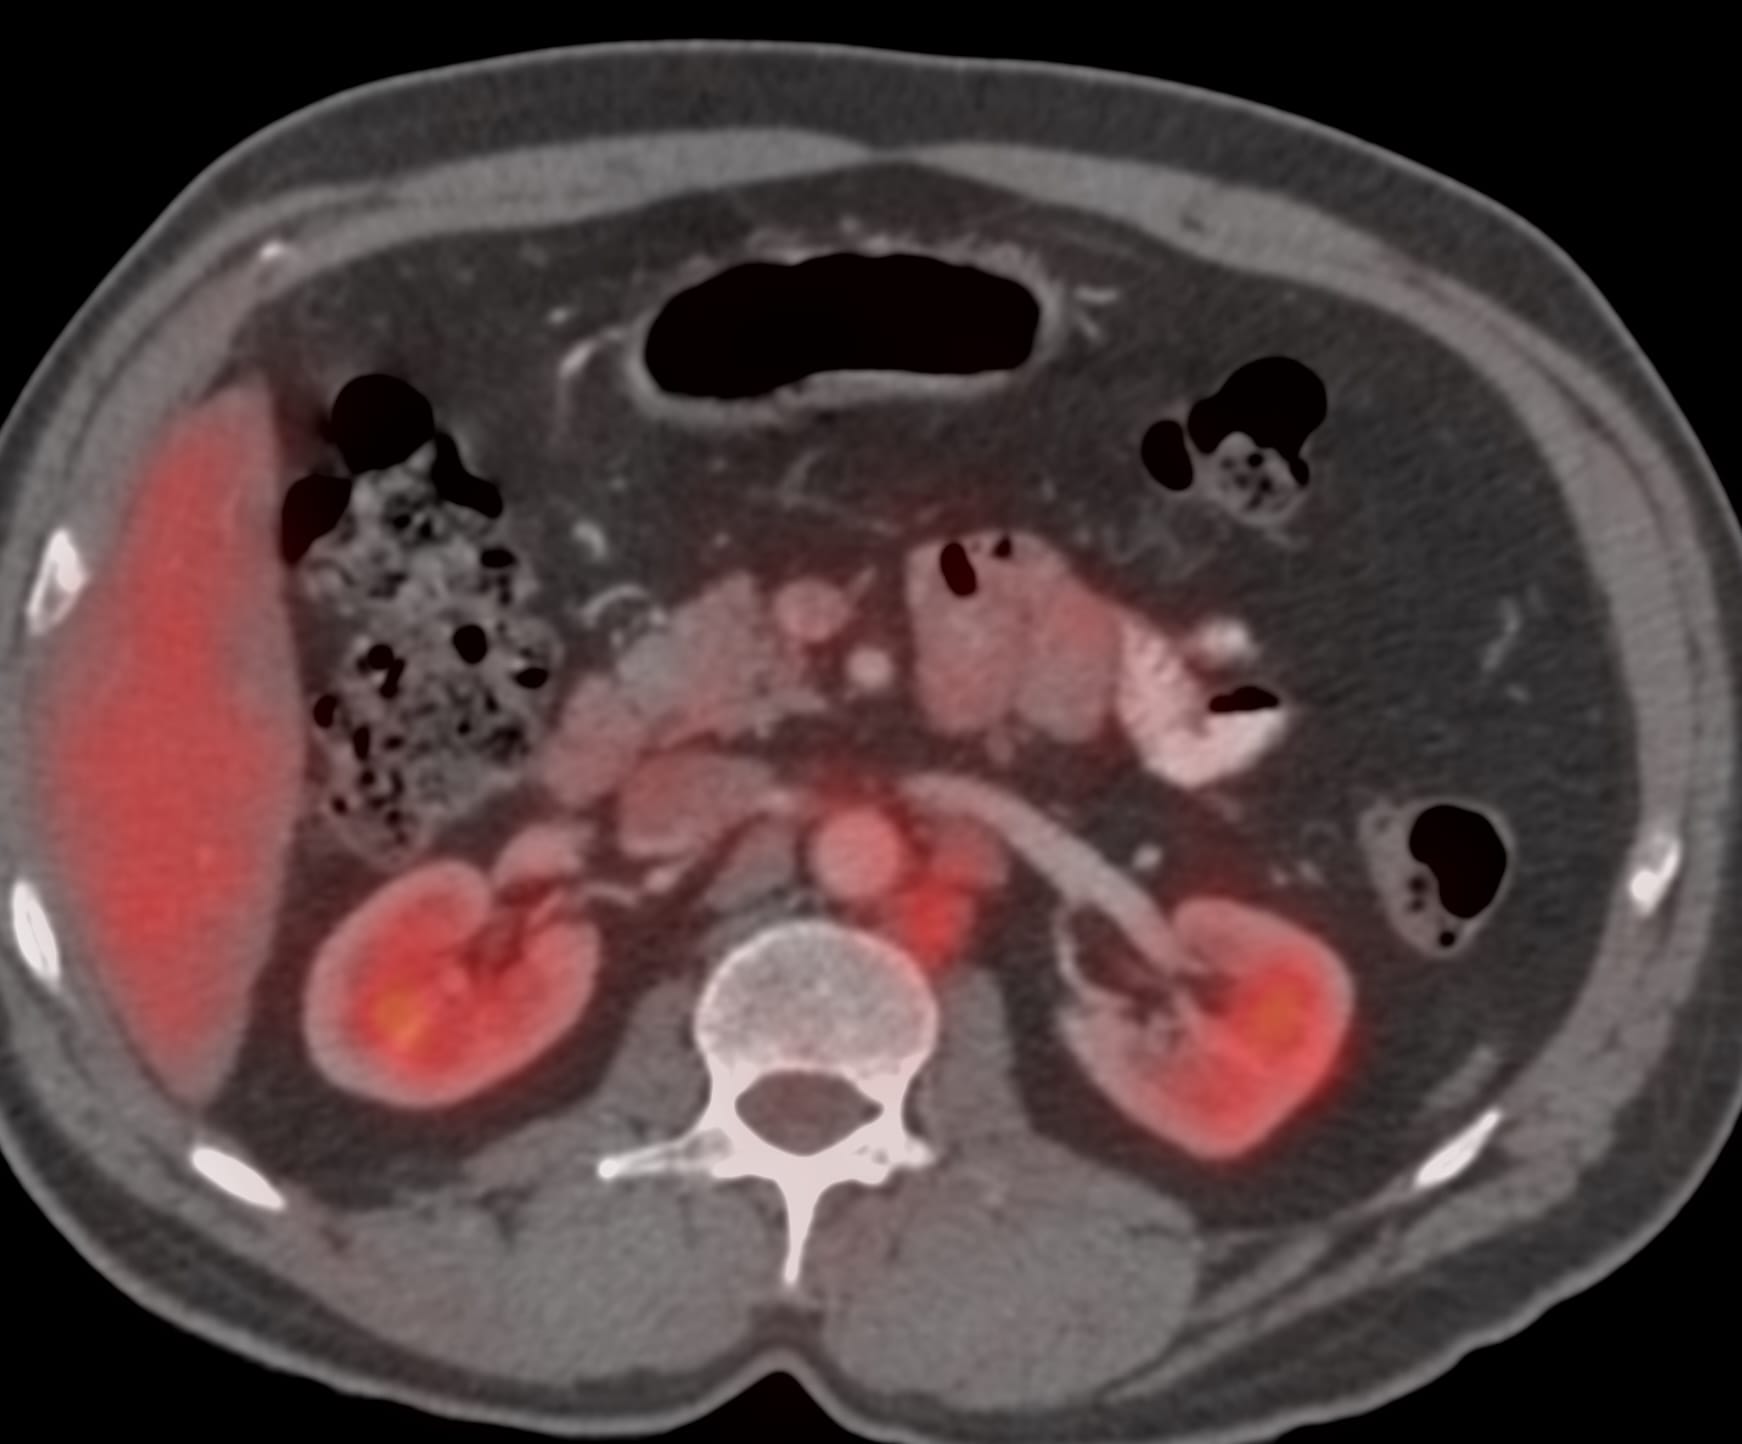

Case 17: 56-years old treated for Ca esophagus had new retroperitoneal para-aortic nodes on PET